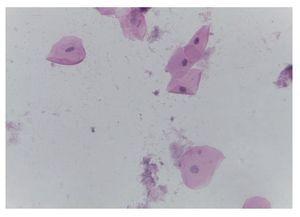

Se encontraron 35 ml de sangre en el hemitórax izquierdo y 25 ml en el pericardio, además de una hemorragia mediastinal. Los cortes histológicos del mediastino mostraron tejido adiposo con hemorragia extensa, restos del timo con corpúsculos de Hassall calcificados y depleción linfoide. Continuando con el mediastino, el corazón tuvo un peso de 100 g vs 115 g. Lo que llamó la atención, desde el punto de vista macroscópico fue una hemorragia petequial en el pericardio, en la aurícula y ventrículos derechos. Visto por su cara posterior se observó la hemorragia en la adventicia de la arteria pulmonar y una hemorragia subepicárdica de 3 × 2 cm. Los cortes histológicos mostraron cardiomiocitos con citoplasma vacuolado, algunos con ligero aumento en el tamaño del núcleo. Esto resulta importante porque la paciente había recibido daunorrubicina, que es cardiotóxico. Sin embargo, no hay cambios histológicos secundarios a la administración de este fármaco. El hígado tuvo un peso esperado de 1600 g contra un esperado de 756 g. Macroscópicamente, se observó un color café claro; histológicamente se observaron muchos cambios, como alteraciones importantes en la arquitectura por la presencia de fibrosis a nivel de las venas centrales, principalmente. A nivel de los espacios porta y de las venas centrales se observaron numerosos hemosiderófagos. En el lobulillo hay esteatosis, y en los sinusoides, también numerosos hemosiderofágos (fig. 4). En el lobulillo, la esteatosis es macro y microvesicular. Estos son datos importantes en la lesión por medicamentos que, al parecer, es lo que se observa en el hígado. La presencia de esteatosis macrovesicular es secundaria a esteroides, y la presencia de esteatosis microvesicular es secundaria a la administración de metrotexate y L-asparaginasa. La fibrosis y el daño que vemos en los espacios porta son secundarios al depósito de hemosiderina tan extenso en esta paciente; además, hay colestasis intracitoplasmática. Se realizó una tinción de Masson donde puede observarse la presencia de puentes de fibrosis, que unen las venas centrales con los espacios porta, dato de lesión irreversible que probablemente progresaría a cirrosis. A mayor aumento es evidente el depósito de colágena IV y VI y la expansión importante a nivel de los espacios porta y de las venas centrales. En una tinción de Perls, específica para ver depósitos de hierro, se puede ver la presencia de hemosiderófagos, con distribución en gránulos gruesos en todos los campos (fig. 5). Resulta importante porque, con base en esto, se realiza la gradificación histológica. Este es un grado IV/IV en la escala de Krause, con presencia de hemosiderina en todos los campos con distribución en gránulos gruesos.

Figura 4 Corte histológico del hígado con fibrosis portal, hemosiderófagos y esteasis macro y microvesicular panlobulillar (H/E 20x).